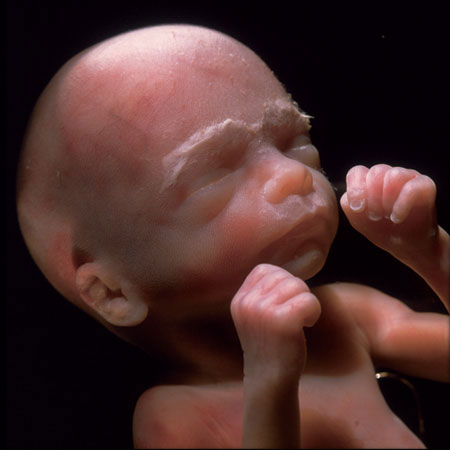

19 недеља

од зачећа 20 недеља